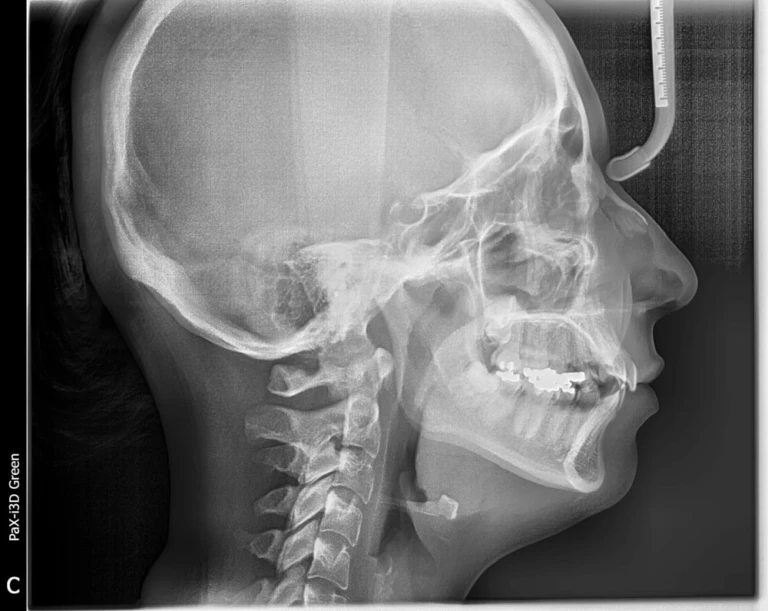

Đọc tiếpClinical excellence: Implant, Piezosurgery, Chẩn đoán hình ảnh, Nội nha sinh học